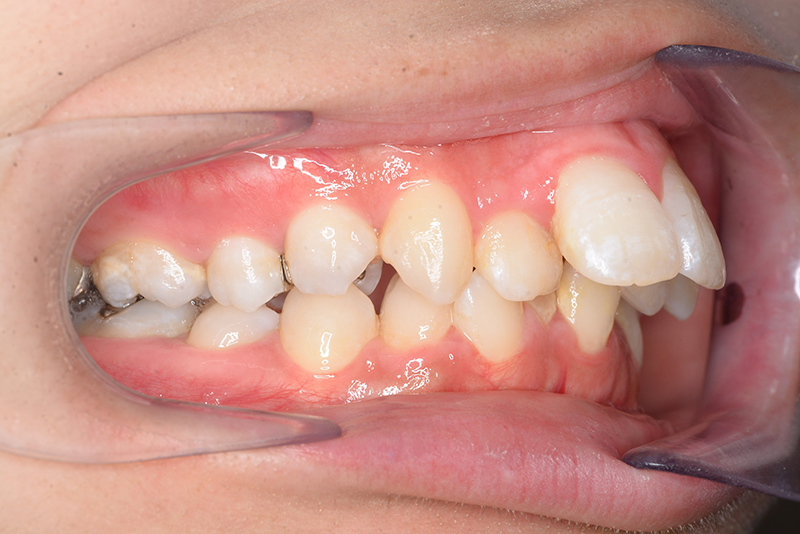

初診時

FP・IOP

口腔内所見 over jet 11.5mm、over bite 5.5mm、右側臼歯関係Full ClassⅡ級、左側end onⅡ級、上顎顎歯列はテーパー型であり、上顎中切歯は押し出されるように大きく唇側傾斜していた。下顎前歯部は叢生を呈しており、左下5は歯冠長が短く半埋伏していた。